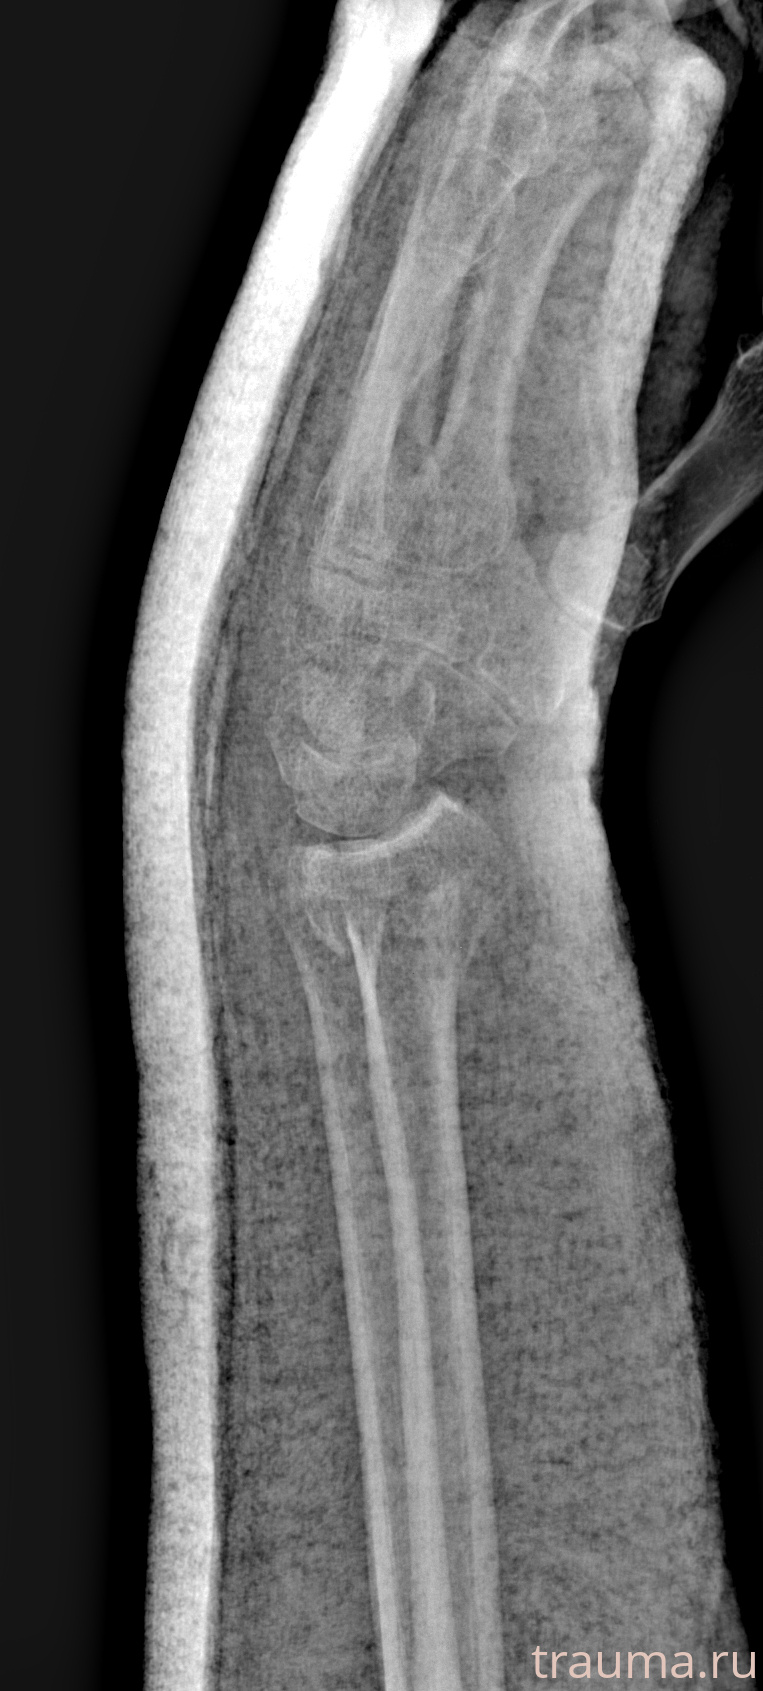

Рентгенограммы

Рентген на дому: по вашему адресу приезжает врач-рентгенолог, травматолог-ортопед с мобильным рентгеновским аппаратом, проводит диагностику травмы или заболевания, делает необходимые рентгенограммы, дает рекомендации по дальнейшему лечению. Получить качественные снимки в домашних условиях возможно благодаря уникальной методике, разработанной МосРентген Центром для института  Склифосовского